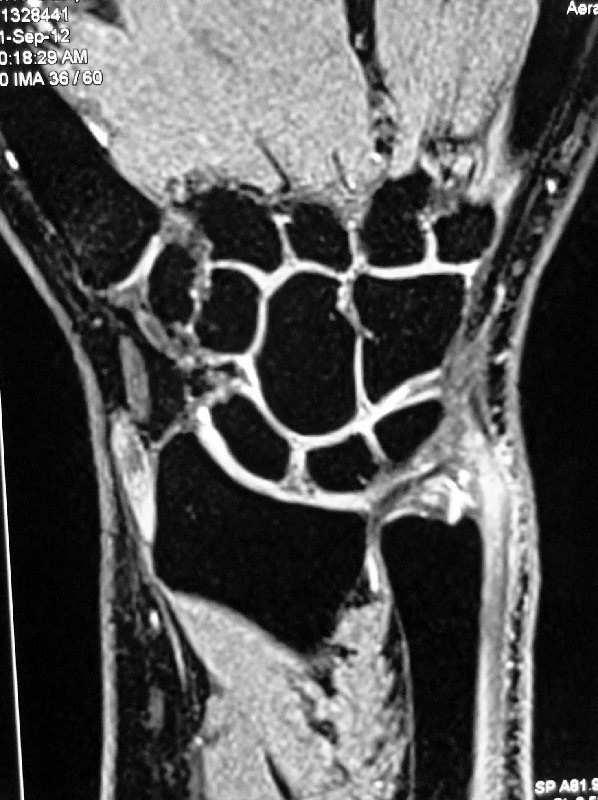

- MRI scan of her wrist showed a TFCC tear.